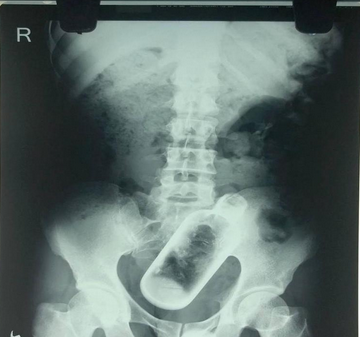

微信扫码关注印度36岁男子Narayan因为腹部和背部疼痛去医院检查,照完X光后在他的直肠部位发现了一个长达16厘米的酒瓶。

医生说,该男子来医院时声称自己时常觉得胃疼、腰背部疼痛。该名男子的熟人说他每天“醉醺醺”,肯定是喝酒时不小心“吞进”了酒瓶。

男子在医院接受了手术,半小时后医生将玻璃瓶从其腹中取出。玻璃瓶将被送到实验室,方便医生做进一步检查。外科病区的部长Gopal Singal表示,他有生以来没见过这么“奇葩”的案例。